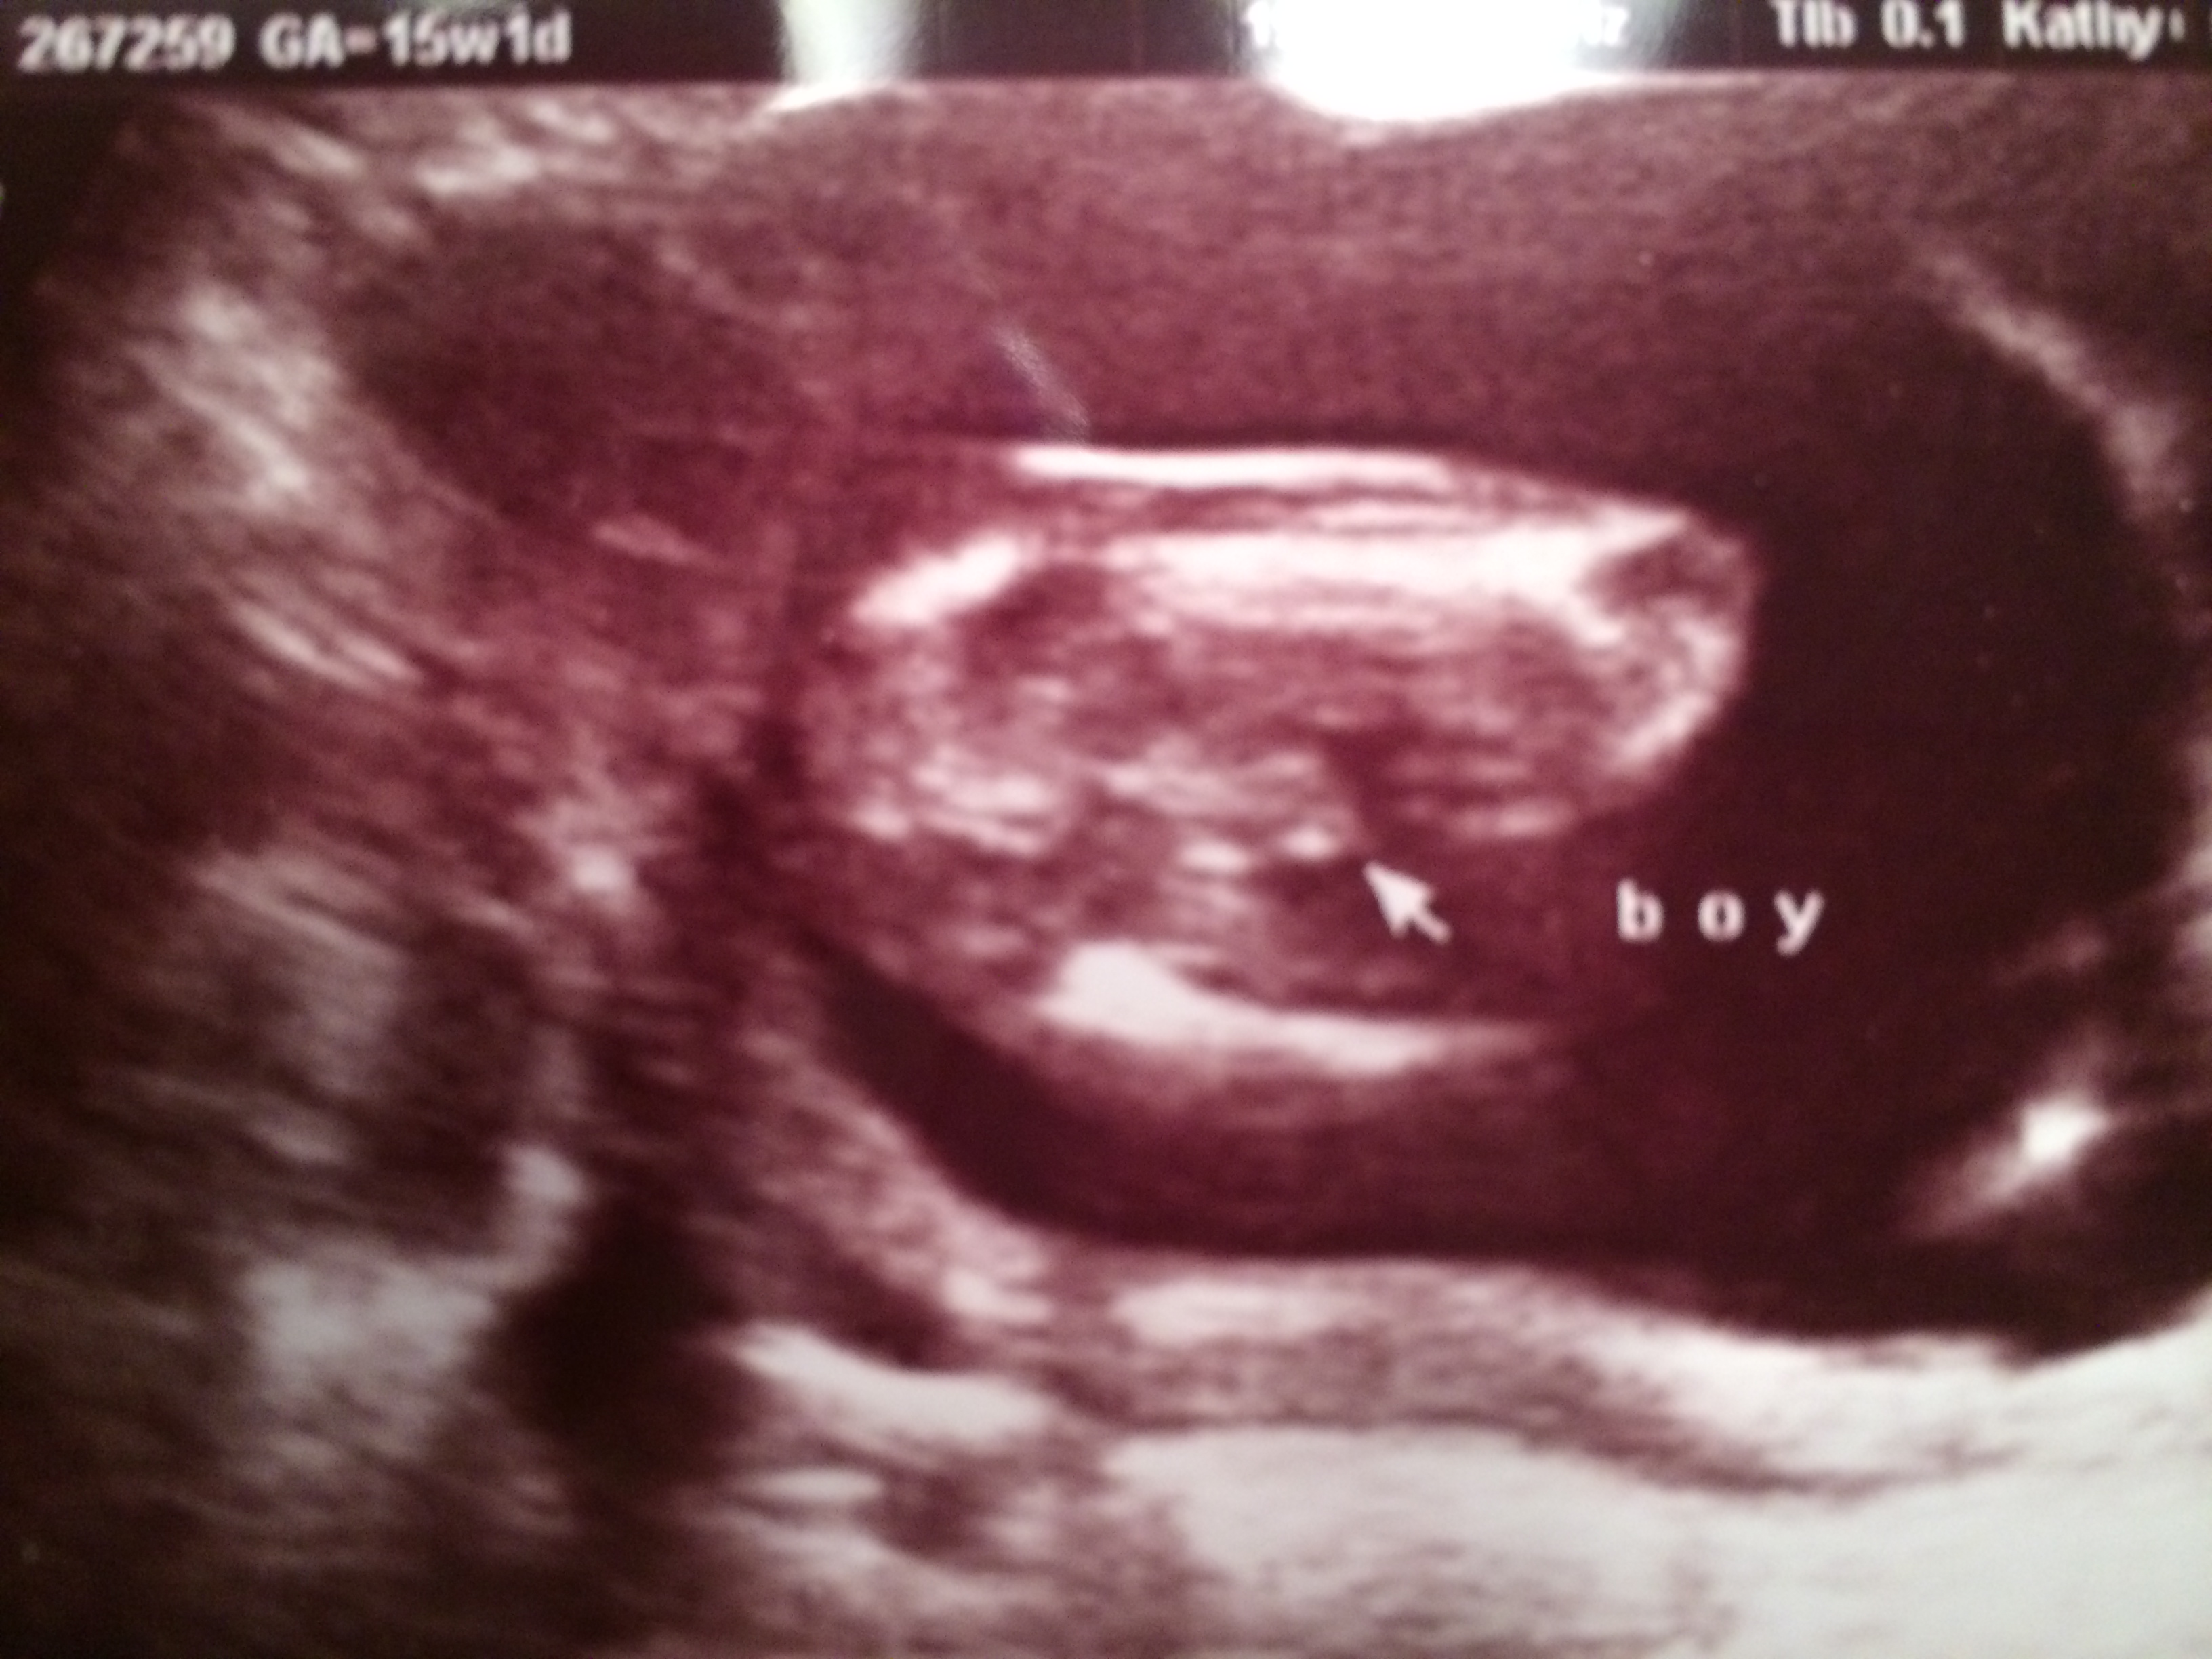

I did. I got an ultrasound at 15 weeks and 1 day and it was clear he was all boy.Attachment 17430

I attached the ultrasound for you. I think you should be able to see your baby and make that special announcement! Good luck to you.